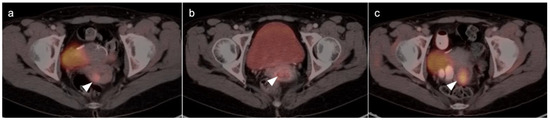

2.6. Vulvar Carcinoma